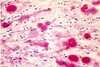

Vilken bakterie?

Staphylococcus aureus

Vad visar bilden?

Streptococcus pneumoniae (diplokocker)